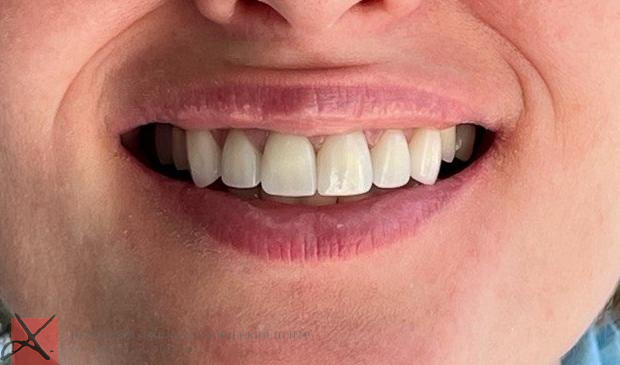

- Разгладились носогубные складки, лицо приобрело более молодое и симметричное выражение

- Улыбка стала эстетичной и гармоничной

Результат лечения